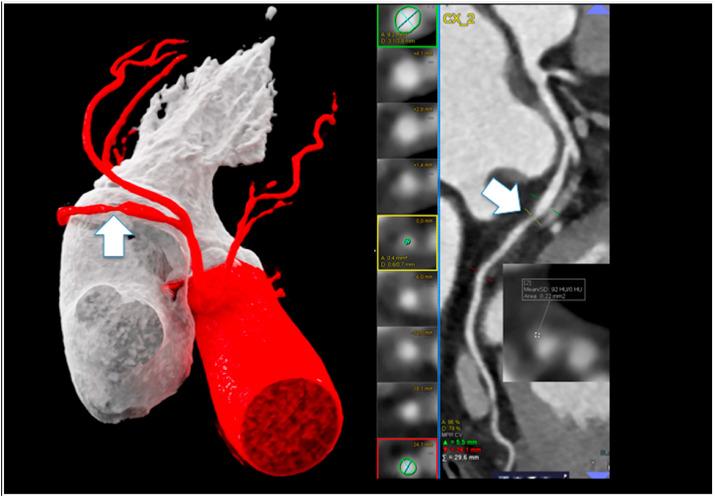

The Journal of Cardiovascular Computed Tomography: 2020 Year in review.

The purpose of this review is to highlight the most impactful, educational, and frequently downloaded articles published in the Journal of Cardiovascular Computed Tomography (JCCT) for the year 2020. The JCCT reached new records in 2020 for the number of research submissions, published manuscripts, article downloads and social media impressions. The articles in this review were selected by the Editorial Board of the JCCT and are comprised predominately of original research publications in the following categories: Coronavirus disease 2019 (COVID-19), coronary artery disease, coronary physiology, structural heart disease, and technical advances. The Editorial Board would like to thank each of the authors, peer-reviewers and the readers of JCCT for making 2020 one of the most successful years in its history, despite the challenging circumstances of the global COVID-19 pandemic.